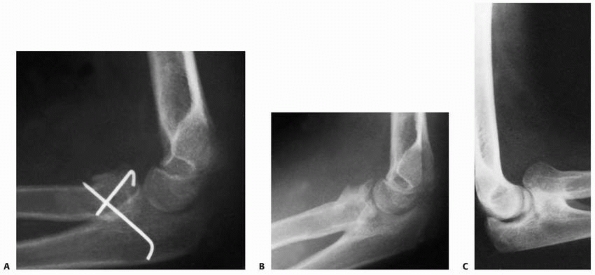

![]() |

FIGURE 11-35 Radioulnar synostosis. A.

Surgical intervention with wire fixation was necessary for a satisfactory reduction in this patient who had a totally displaced radial neck fracture. B. Six weeks after surgery, there was evidence of a proximal radioulnar synostosis. C. Radiograph taken 6 months after reduction shows a solid synostosis with anterior displacement of the proximal radius. (Courtesy of R. E. King, MD.) |